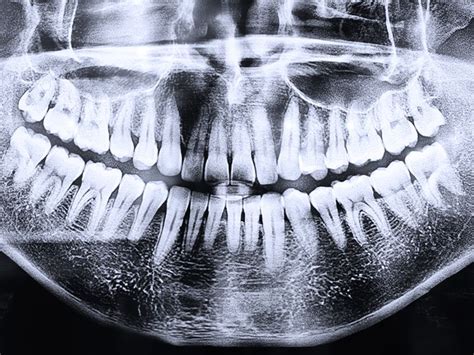

Nuestra labor es que tu primer contacto con nosotros sea agradable y sobre todo familiar, eliminando los posibles nervios iniciales y ayudándote a resolver todas tus dudas. El segundo paso a seguir, es hacerte una radiografía panorámica para dar un mejor diagnóstico. Después de realizarte la radiografía panorámica nuestros especialistas te harán una exploración minuciosa del estado de tu salud bucodental y poder proponer el mejor plan de tratamiento a tus necesidades.